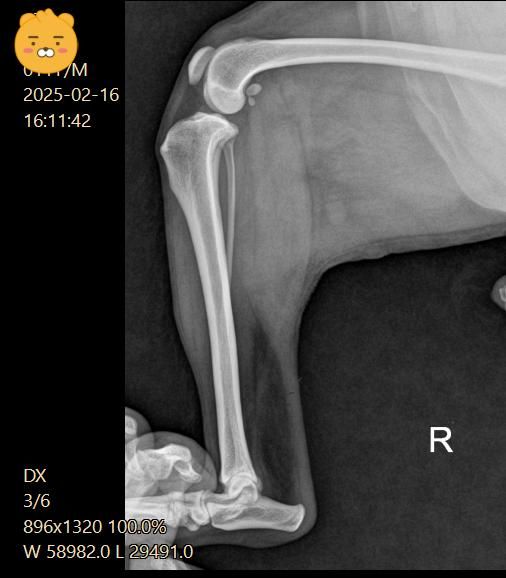

5일 간격으로 엑스레이를 찍었어요

5일후 진료는 십자인대는 애매하고 슬개골 2기로 수술 권유 받았어요

십자인대는 열어봐야 알 것 같다고 하셨고요

(두번째 진료)

우측 관절낭이 좌측에 비해 종창 되어 관찰되고 경골 경사면 각도가 비교적 크게 관찰되어 십자인대에 손상이 있을 가능성이 있는 사진입니다. 이를 확인하기 위해서는 MRI 촬영이 필요하지만 현실적인 검사 방법은 아니라 추정일 뿐입니다. 하지만 방사선학적 관점에서 십자인대의 인장성 손상은 합리적인 추론입니다.